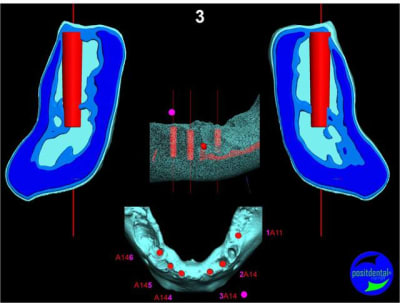

Extraction, pose d’implants Ankylos, pose des piliers Standard définitifs, mise en charge immédiate bi-maxillaire en une chirurgie.

Maxillaire inferieur – extraction 35, 34, 44, 45, 6 implants MCI, comblement osseux, bridge provisoire sans fausse gencive avec renfort métallique.

3D

Préopératoire

uniquement le scan pré-op

en attendant la pano voici les coupes de la S.I.A.O.